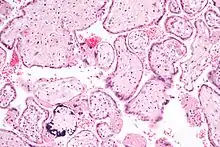

Micrograph of CMV placentitis